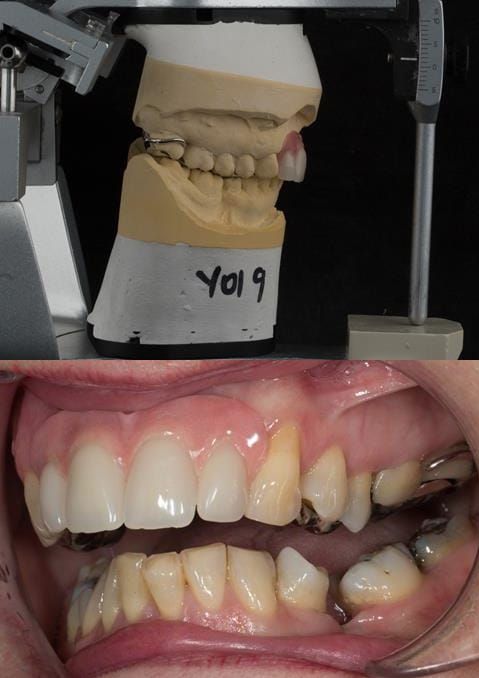

Provision of a maxillary cobalt chromium based partial denture/protective occlusal splint in a heavily restored dentition

- Extract the upper 2-2 teeth and replace with an interim acrylic based partial denture. Reline the interim denture over 9 - 12 months, replacing with a definitive cobalt chromium based partial denture. The definitive denture would ideally be designed as an occlusal protective splint to reduce the the potential for mechanical wear and breakages of the moderately/heavily restored maxillary dentition. In addition, should further upper teeth require extraction they could be added on to the denture cobalt chromium framework - therefore a new prosthesis would not be required as future teeth are lost. This option would produce an excellent aesthetic outcome. This is the option the patient chose to have.

Following consultation and second discussion appointment the patient chose to have option 3 namely, a maxillary cobalt chromium based partial denture/protective occlusal splint. The clinical situation and treatment process is shown in detail below with photographs. The patient was successfully rehabilitated with this and her quality of life considerably improved. The clinical work was provided by Finlay and the technical work by Rowan.